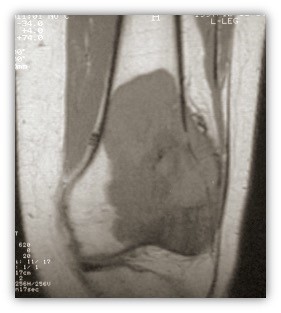

Η απεικόνιση των βλαβών πρέπει να κατευθύνεται από τον Ορθοπαιδικό Χειρουργό και ακολουθεί μία συγκεκριμένη μεθοδολογία.